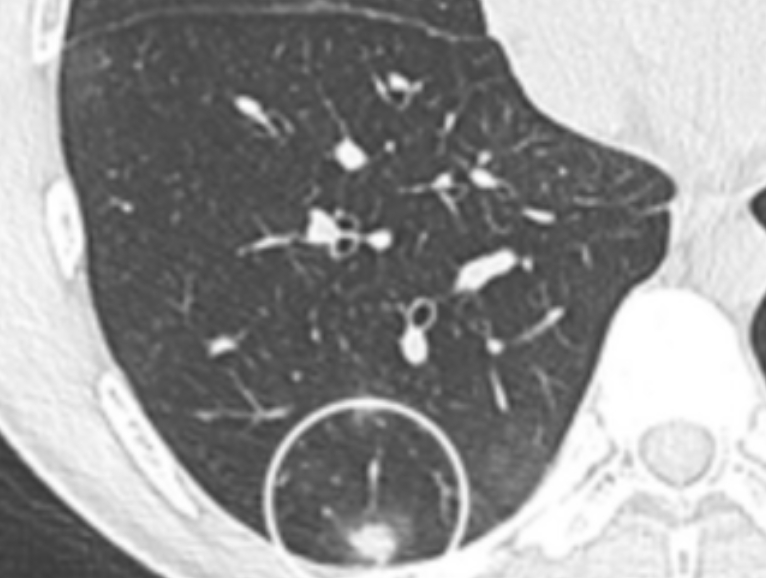

폐결핵 검사

폐결핵이 의심될 때는 흉부 X선과 객담(가래) 검사를 함께 시행합니다. 가래를 현미경으로 관찰해 결핵균이 있는지 확인하고, 배양검사를 통해 균의 종류를 알아냅니다. 최근에는 유전자 증폭검사(PCR)로 조기에 결핵균을 찾는 방법도 많이 사용돼요. 또한 잠복결핵 여부를 확인하기 위해 IGRA 검사(혈액검사)나 투베르쿨린 피부 반응검사도 합니다. 이 검사는 증상이 없어도 과거 감염 여부를 확인할 수 있어요.

검사 결과를 종합해 활동성인지 비활동성인지 판단한 후, 치료 방향을 정하게 됩니다.